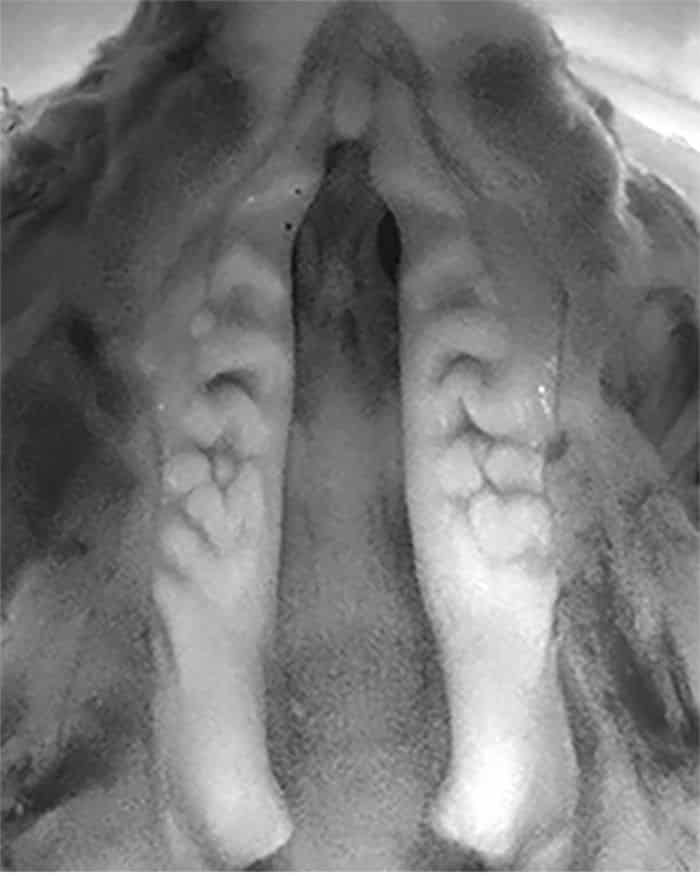

و بكيفية تشبه حدوث الحنك المشقوق في الإنسان، فإن الفئران المصابة تعاني أيضا من عدم التحام أنسجة الحنك في خط المنتصف عندما يكون لديها نقص في الجين PAX9.

و قد أدى العلاج إلى استعادة عملية التحام الحنك في كل الفئران التي تم اختبارها.